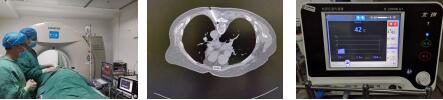

今年七月中旬,疼痛科收入住院,對患者進行“胸椎硬膜外連續(xù)自控鎮(zhèn)痛”治療。4天后,副主任醫(yī)師王中勝帶領白長敘醫(yī)生對患者實施了目前臨床上先進的彩超聯(lián)合CT引導下胸5-7神經(jīng)射頻調(diào)節(jié)術(微創(chuàng)手術),這個技術對病變受累神經(jīng)功能進行直接調(diào)節(jié),從而能達到很快地明顯改善患者的疼痛和各項臨床癥狀,經(jīng)過1個多周的治療,患者疼痛明顯緩解,滿意出院。

郭阿姨就診時:疼痛評分6分。

市中醫(yī)院疼痛科治療方案:

第一步:胸椎硬膜外連續(xù)自控鎮(zhèn)痛+對癥藥物治療

第二步:彩超聯(lián)合CT引導下胸5-7神經(jīng)射頻調(diào)節(jié)

治療結果:疼痛評分為1—2分,疼痛明顯緩解,效果顯著,由入院時的焦慮不安到出院時微笑滿面,患者十分滿意。